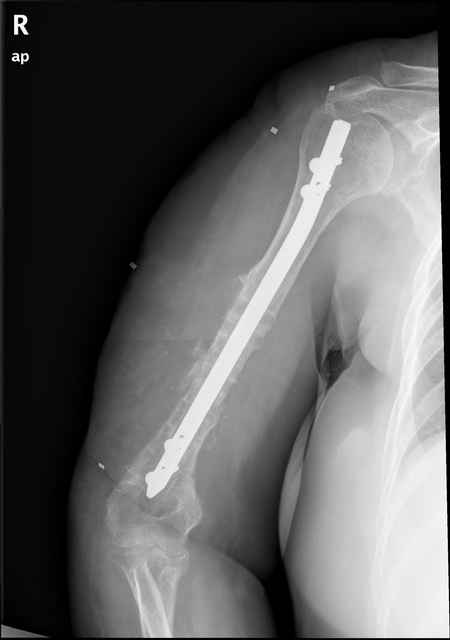

Несращение диафиза плечевой кости |

Больная 48 лет, медсестра-массажист, перелом плеча 7 лет назад, оперирована 4-кратно и безуспешно

Больная 48 лет, медсестра. Травма получена 7 лет назад, оперирована первично в Турции - остеосинтез пластиной - несращение - реостеосинтез стержнем там же через год (обычным, с выстоянеием его в полость плеча) - несращение - поступила к нам впервые в марте 2008 года - удаление стержня, реостеосинтез пластиной и костная пластика, в течение 2 лет лизис кости вокруг винтов, смещение фиксатора, в марте 2010 - удаление пластины, реостеосинтез интрамедуллярным стержнем с блокированием (рассверливание + костная пластика). В динамике - вновь лизис в области перелома, нестабильность дистальных блокирующих винтов.

Два отягощающих момента:

(1)после первых операции имелся неврит лучевого нерва - в настоящее время все ОК и

(2) лет 9 назад оперирована по поводу заболевания молочной железы с той же стороны с облучением.

Вопрос: как стимулировать сращение в сложившейся ситуации?